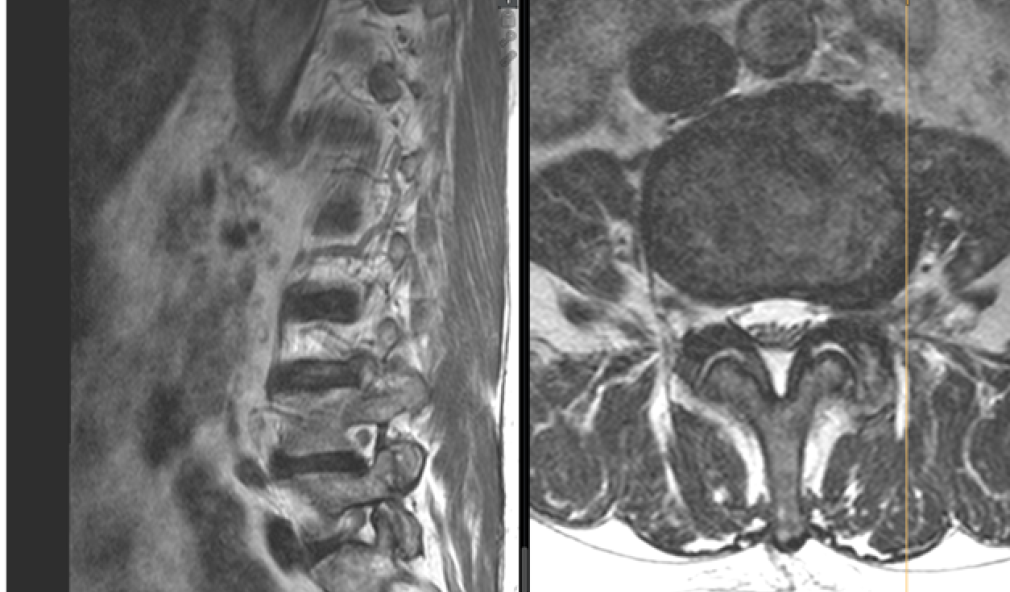

Research award: Successful therapy for painful lateral disc herniation from a patient’s perspective

A Schulthess Klinik research group has received the «Outstanding Special Poster» award from the International Society for the Study of the Lumbar Spine for its research report on a therapy for painful lateral disc herniation.